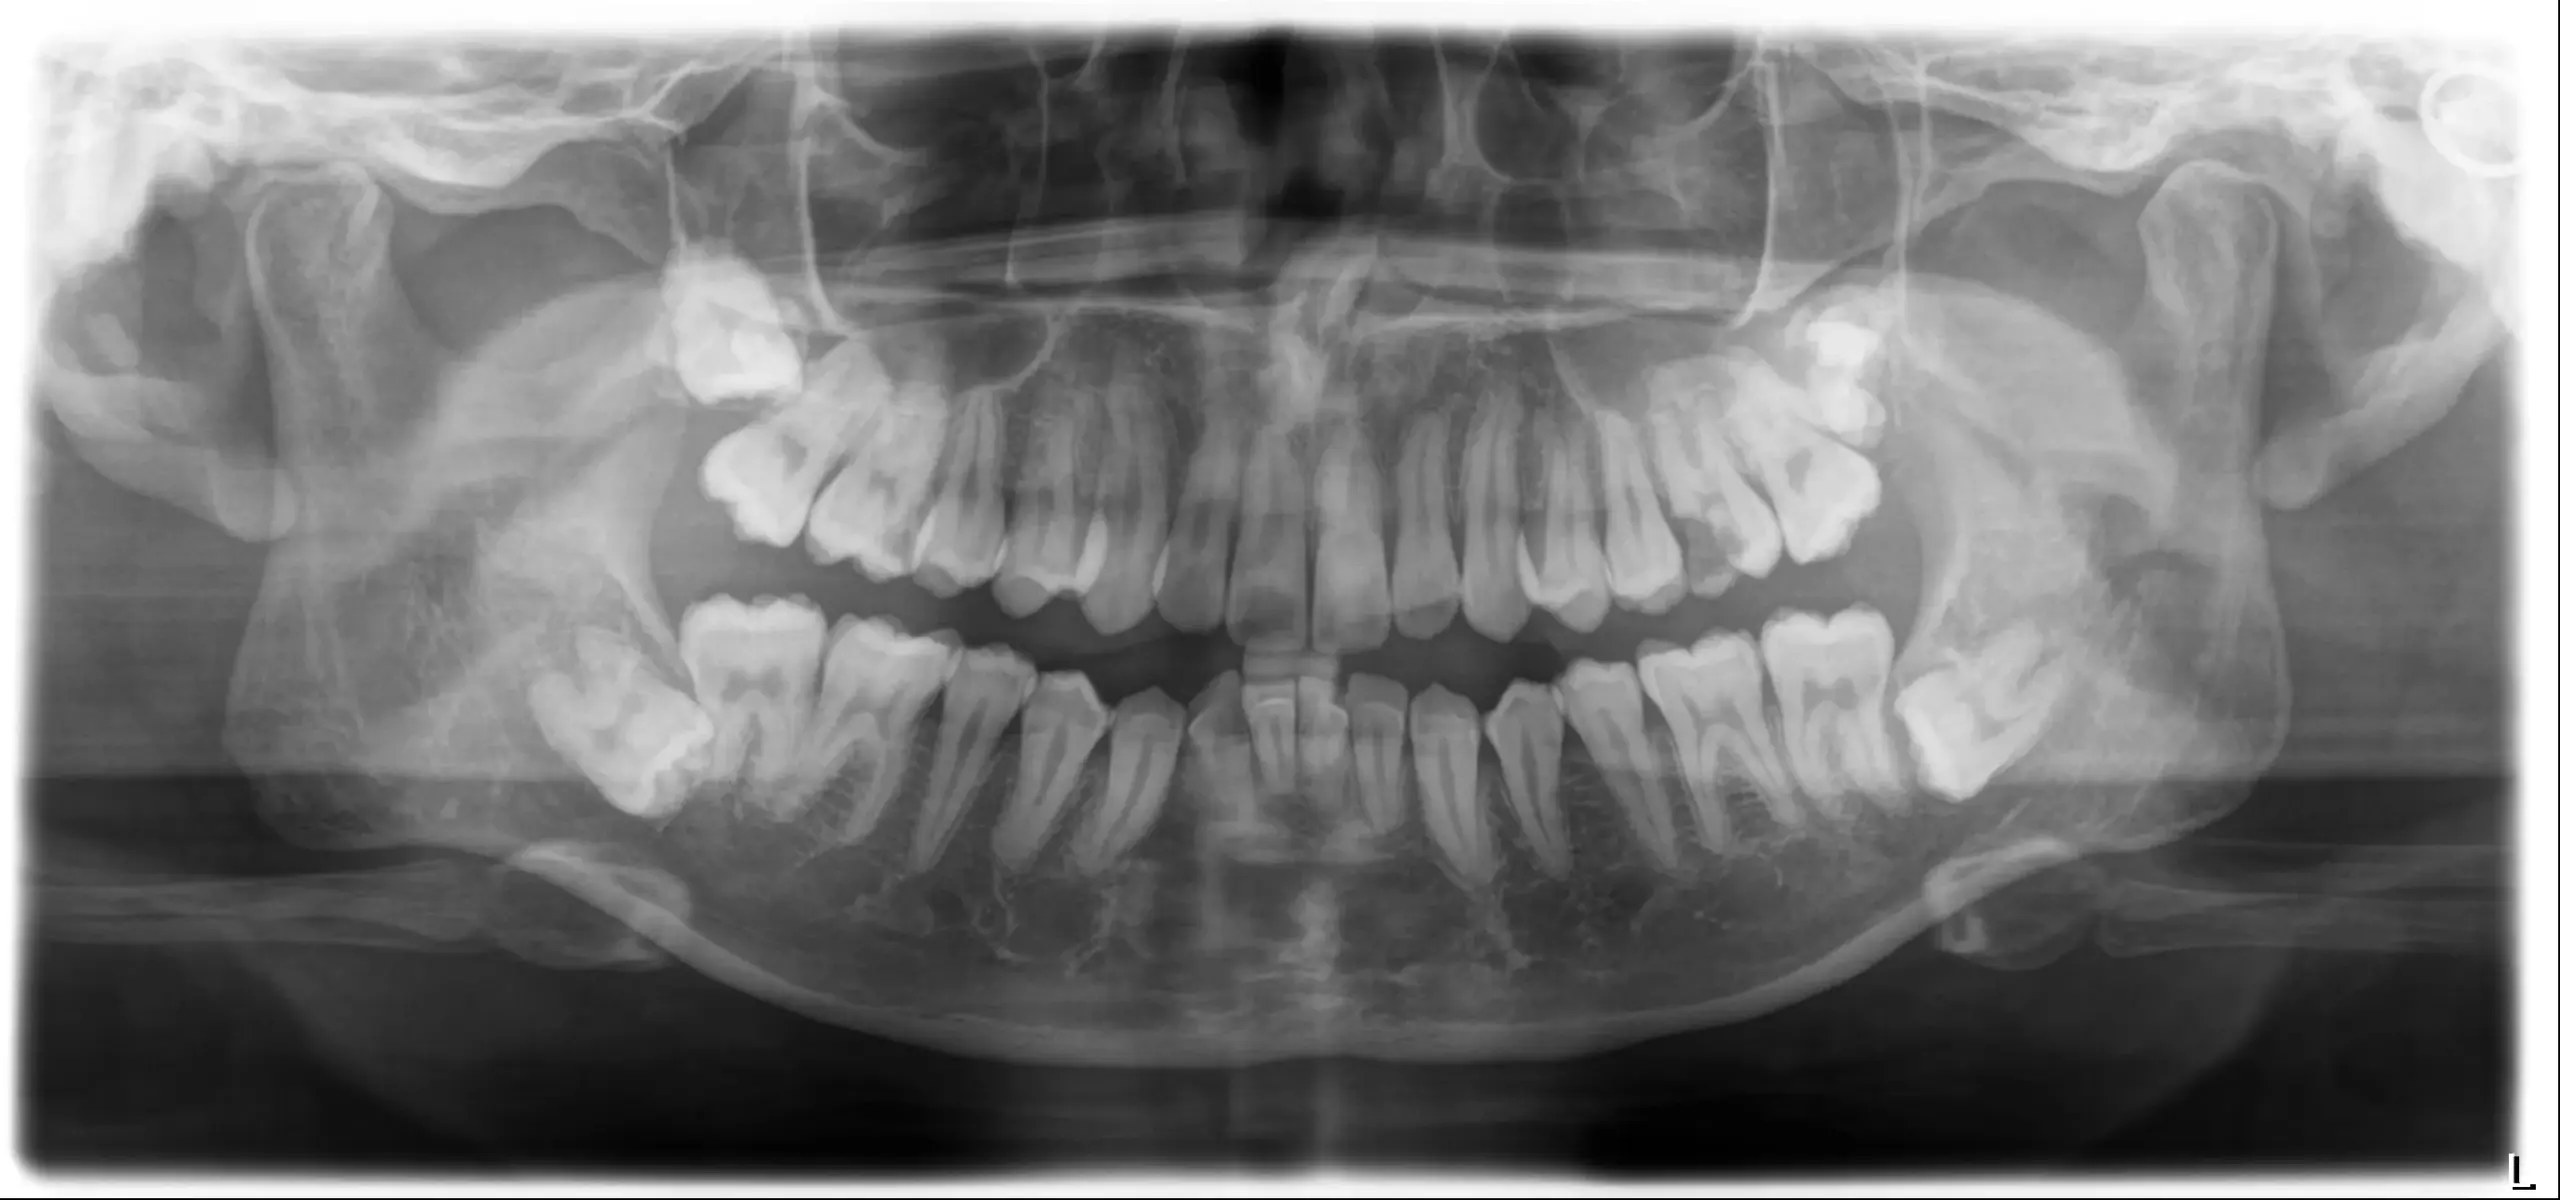

before

after

CASE 01

精密根管治療